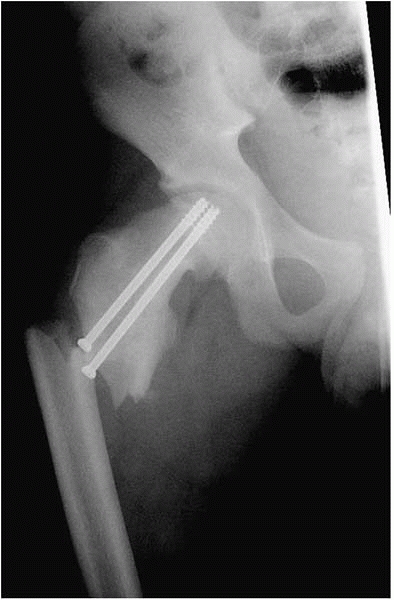

![]()  |

▪ FIGURE 22-13

An essential part of staying out of trouble after SCFE fixation is careful intraoperative evaluation of the screw placement. Importance of a true lateral approachwithdrawal technique. This screw looks perfect on the AP (A) and semilateral (B). However, this image (C) shows threads out. The time to discover this is in the operating room, not months later in the clinic (see Fig. 22-14).  |